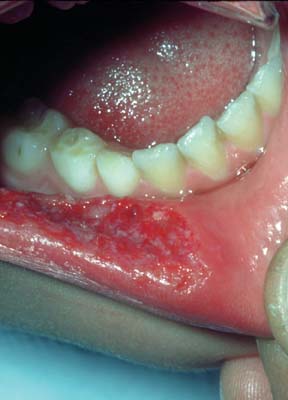

Self-induced soft tissue injury caused by lip and cheek-biting is an unfortunate complication of local anesthetic used in the mouth and is usually self-limiting and heals without complications, although bleeding may result. The frequency of self-induced soft tissue injury is higher when only one side is anesthetized. To help avoid the possibility of soft tissue injury, patients and their parents or caregivers need to be especially watchful and not allow the patient to bite, suck, or scratch on their lip, cheek, or tongue, and do not allow them to eat food while the anesthesia persists (still numb). If an injury does occur, it is best to cleanse the mouth with either OTC Peroxyl rinse, or warm salt water. If necessary, Tylenol or Motrin can be used to alleviate pain while the area is healing.